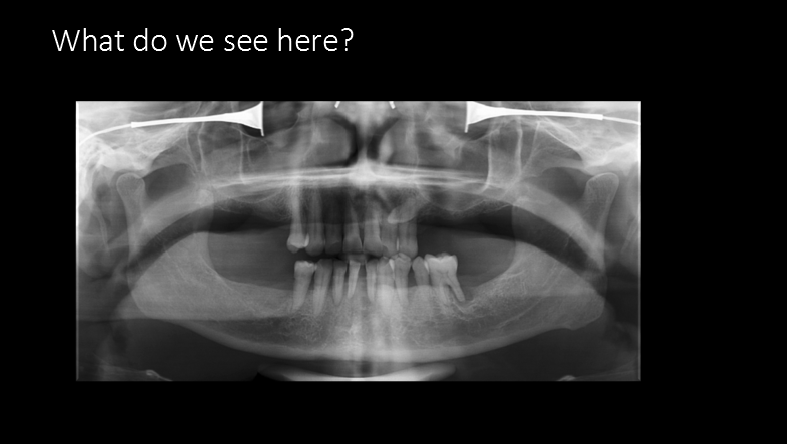

What do we see here?

What Zone Is This?

Zone 1: Dentition

What do we see in Zone 1?

supernumerary teeth/impacted tooth